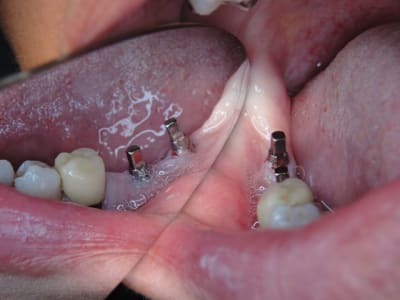

A défaut d'une chir en direct .. voilà une petite histoire en photos ou comment en 90 minutes passer d'un partiel résine à ...7 implants sur provisoires..stabilité primaire 60N grace à la technique MIMI ( oui.. post spécial ce Week end)..:)

Il n'y a jamais de questions stupides. Merci à ceux qui s'interrogent ..donc les hauteurs de s'interrogent caps existent mais pour gérer l'enfoncement de l'implant et pour aussi proposer des différentes hauteur de pilier : autrement formulé en fonction de la position de la rainure de la gérer carrée on a deux millimètres de marge/niveau gingival selon le choix du prep cap. Cela permet de placer le prep cap lorsque l'implant a du être enfoncé plus profondément ou bien si la hauteur de gencive est plus importante que les deux millimètres classiques de l'espace biologique usuel. (description sur le site du fabricant...shop online entre autre.)

Exp dans ce cas 4,5/10mm en 36 dans un site d'extraction récent placé en 12mm soit deux millimètres plus profondément j'ai scellé un prep cap angulé 5 degrés niveau 1/0 dont la limite s'arrête à la rainure de la tête carrée, pour 37 3,5/10mm placé en 10mm j'ai utilisé un prep cap 2/2mm. On prend vite l'habitude moi j'utilise que 2 modèles en zircone et 3 en titane..

Maintenant concernant la demande de scans : je poste ce cas, une patiente vient me voir avec son scan car elle a consulté d'autres "spécialistes" et on lui refuse la pose d'implant secteur 4 où alors avec greffe préalable..Ca se discute..pas de temps à perdre je sais faire autrement..

Avec la chir trans gingivale technique MIMI ( Oui..un post sur la technique bientôt ..) j'ai pu placer deux 3,5/8mm..aurai je eu le meme résultat avec un lambeau..j'en doute..Les couronnes sont en titane. Recul clinique 2 ans ras. Simple efficace rapide moins onéreux satisfaisant pour le praticien et la patiente..